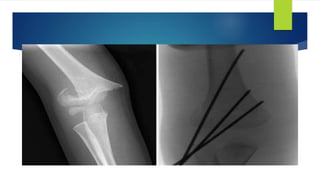

 The protocol initiated for surgical technique included the placement of two lateral

pins after reduction was obtained. Then, the fracture was stressed and analyzed

radiographically. If the fracture was stable, a third lateral pin was placed. If there

was motion at the fracture site, then a medial pin was placed. The attending

surgeon made this determination.

 The number and configuration of pins that were placed per patient in 2006-2008 was

compared to the number and configuration of pins that were placed per patient in

2009-2011. In addition to the number of pins placed, the location (medial vs. lateral) of

pin placement was compared between the same set of years.